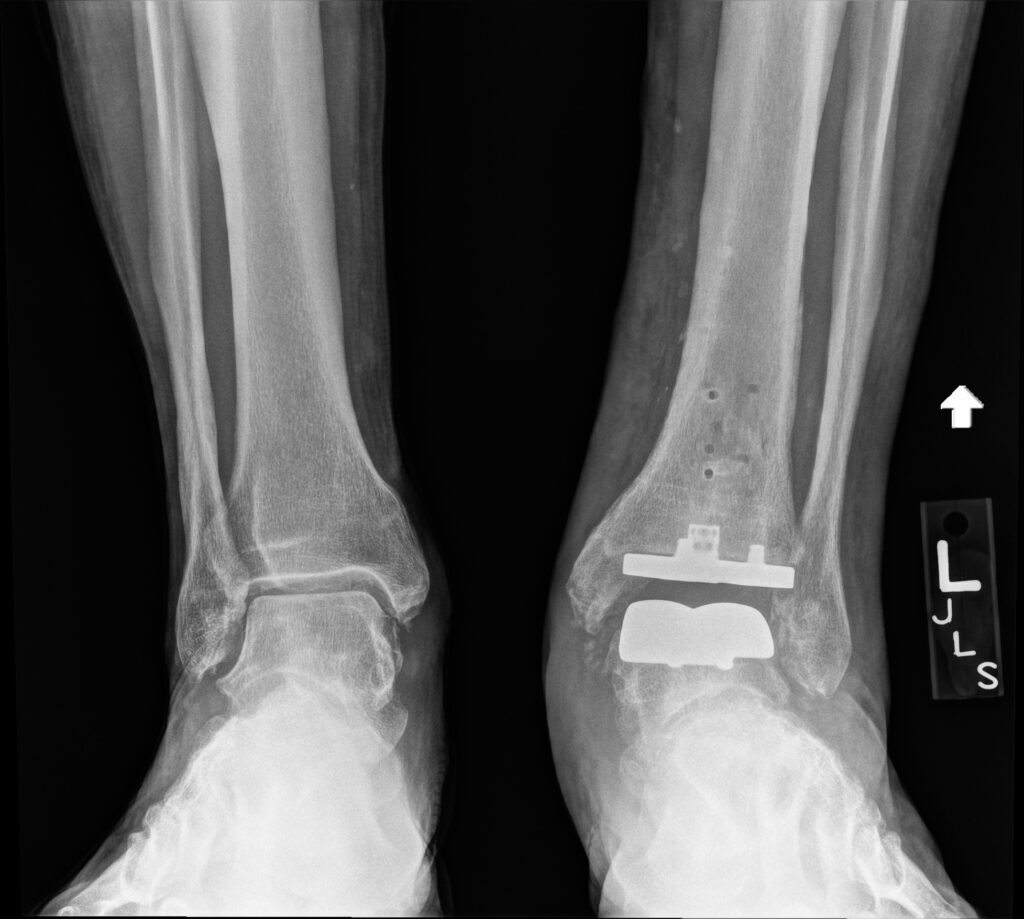

“To qualify for the name, OG Replacement Parts, I needed replacement parts.” His fall also damaged his knees, and he had a partial right knee replacement in the fall of 2021 and then a total ankle replacement (the fifth surgery on the left ankle) in December 2023. “I came up with the name myself, having switched it from Chinbanger, which was created after I flipped over my bike and smacked my chin into a concrete sidewalk.”